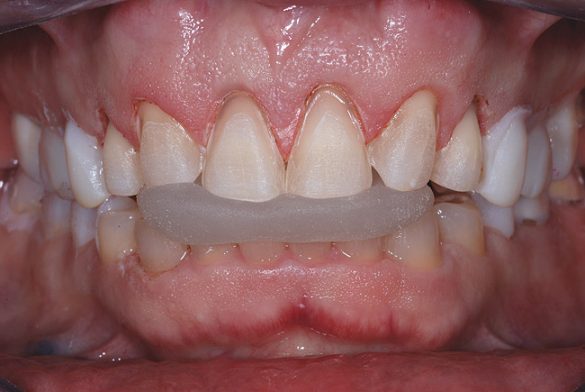

După finalizarea tratamentului ortodontic s-au îmbunătăţit simetria, lăţimea arcului, alinierea şi funcţia, urmând planificarea zâmbetului şi faza chirurgicală.5 Examinarea clinică după tratamentul ortodontic a evidenţiat o ocluzie long centric cu suprafeţe ocluzale plane, făcând dificilă obţinerea unei înregistrări reproductibile a ocluziei. Utilizarea unui arc facial de transfer şi înregistrarea relaţiei centrice pentru a monta anatomic modelele preoperatorii a constituit un important pas de bază. Acesta s-a realizat utilizând un deprogramator anterior simplu, care permite raportarea anatomiei şi ajută astfel la obţinerea unei înregistrări repetabile şi clare a ocluziei.6

Următorul pas logic era determinarea poziţiei muchiei incizale ideale a incisivilor centrali cu buzele în repaus, prin efectuarea unui mock-up intraoral din compozit. Compozitul fluid reprezintă o bună opţiune pentru adăugarea provizorie la muchiile incizale şi/sau la acoperirea ţesutului pentru testarea diferitelor schimbări, vizualizarea rezultatelor proiectate şi pentru a obţine acceptul pacientului. Prin adăugarea compozitului la ariile gingivale şi incizale ale dinţilor 1.1. şi 2.1., s-a stabilit o nouă formă incizală pe care pacientul a aprobat-o. S-a verificat fonetica şi afişarea corespunzătoare a unei lungimi de 2-3mm, cu buzele în repaus9 (fig. 2).